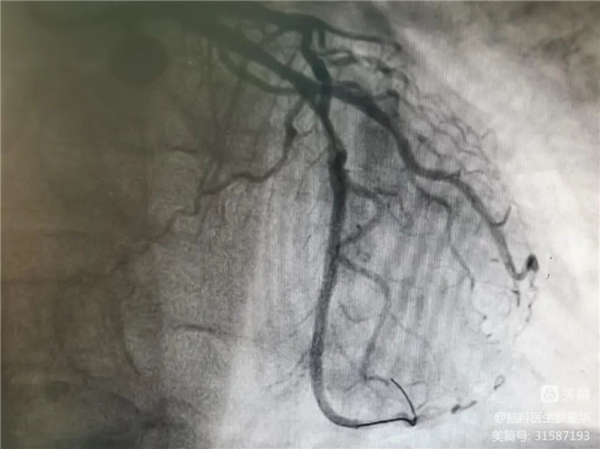

支架植入后狹窄完全解除